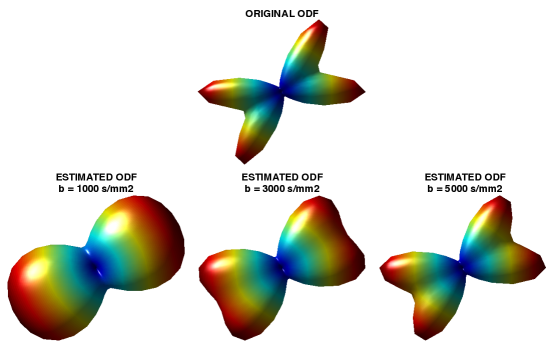

The nature of single-shell acquisition inherent in HARDI imposes constraints on the directional resolution of estimated ODFs, with higher values of the diffusion scintillation parameter (the so-called -value) leading to better resolvability between various diffusion modes within a given voxel. This fact is exemplified in Fig. 1, which shows a simulated ODF111The ODF was generated using a standard Gaussian mixture model [23] with equal volume fractions, FA=0.8 and MD = mm2/s. (top subplot) corresponding to two fibre tracts crossing each other at an angle of o. At the same time, the bottom row of subplots depict the ODFs which have been recovered from the associated HARDI data generated with s/mm2. One can see that the best directional resolution is attained at the maximum value of = 5000 s/mm2, as expected. It is also worthwhile noting that the above effect is intrinsic in both the Funk-Radon transform (FRT) [22] and solid angle [27, 29] formulations of QBI.